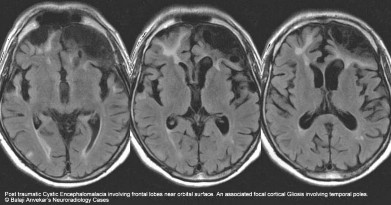

Hình 1.10. Tổn thương não sau chấn thương sọ não dạng nang dịch và tăng sinh thần kinh đệm khu trú

Nguồn trích dẫn: Hiba AH, Lawrence JH. Uptodate. 2018; Topic 14040 [29].